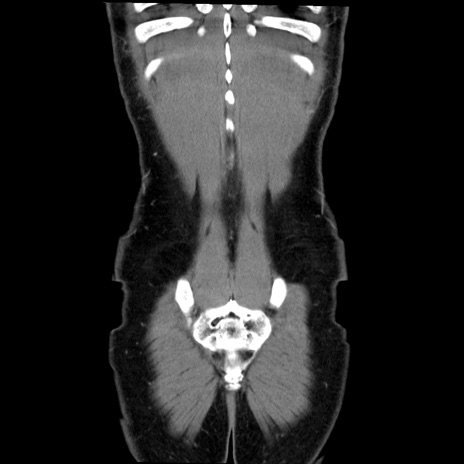

症例36(冠状断像)

【症例】20歳代 男性

【主訴】心窩部痛

【現病歴】今朝より上腹部痛あり。一旦軽快していたが再度出現したため救急要請。昨日夕に白身の魚を含む刺身を食べた。

【身体所見】BP 136/89mmHg、HR 74/min、BT 37.0℃、腹部:膨満、軟、心窩部に圧痛あり。反跳痛なし、筋性防御なし、腸雑音やや亢進あり。

【データ】WBC 17700、CRP 0.48